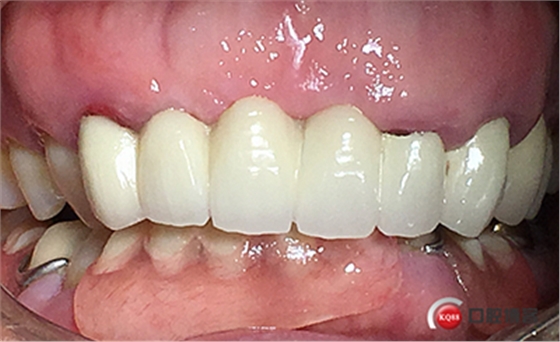

戴牙。

戴牙后半年復查。